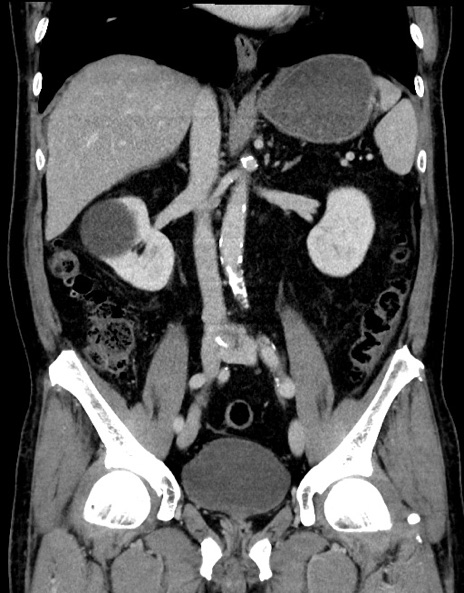

症例15(冠状断像)

【症例】70歳代男性

【主訴】腹痛

【現病歴】今朝から腹痛あり。全体的に痛い。特に左上の方。排ガスが今日はない。冷や汗が出る。

【既往歴】直腸癌術後

【身体所見】左側腹部〜上腹部に圧痛あり。腹膜刺激症状明らかなではない。軽度反跳痛。左下腹部に術後瘢痕あり。

【データ】WBC 7700、CRP 0.02